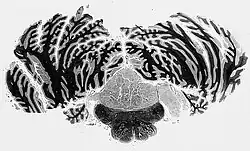

Podwyściółczak (łac. subependymoma, ang. subependymoma) – pierwotny guz ośrodkowego układu nerwowego, o bardzo małej złośliwości (I° według WHO),wywodzący się z macierzystych komórek glejowych różnicujących się w kierunku ependymocytów lub astrocytów. Klinicznie i histologicznie przypomina wyściółczaka (ependymoma). Bardzo długo rozwija się bezobjawowo i częściej rozpoznawany jest w badaniu sekcyjnym niż przyżyciowo. Typowo lokalizuje się w okolicy IV komory mózgu, w sąsiedztwie otworów bocznych (Luschki) lub w komorze bocznej w okolicy rogów czołowych. Leczenie jest chirurgiczne.